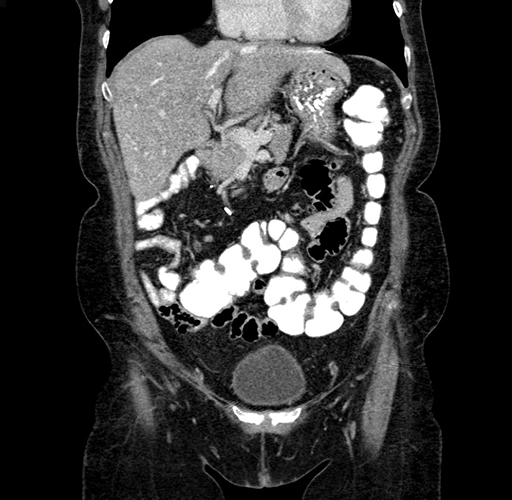

Pre-Chemo: Coronal Venous

Coronal Venous